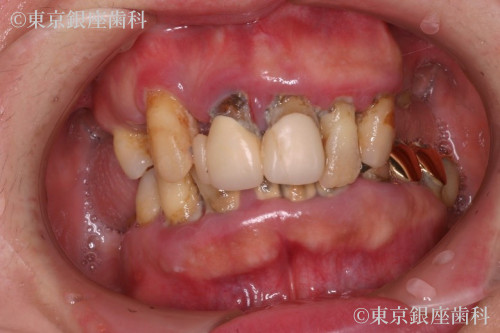

歯周病とむし歯によって咬合崩壊 上下ワンデイインプラントにて再構築した症例

Before

子供の時から歯が弱く通院を繰り返していたが、最近は人に見られるのも嫌で痛みのある時しか歯科に行かなくなった。奥歯が抜けてしまい食事ができない。口臭も気になるので人と対峙して話すことも控えるようになり仕事の面でも支障をきたす。歯肉が腫れたり、歯磨きしても痛いときがある。

症状の経過と現在の状態

痛みが出たり不具合があればその都度費用もかけて治療。しかし歯科医院の転院を繰り返していて定期健診等は受けていなかった。

歯周病の進行で歯に動揺があり長期の保存が難しく、臼歯の欠損で咬み合わせが下がって前歯部への負担が大きくなっているため全顎的な治療が必要と判断。最小限のインプラント埋入によって咬合を回復させるため上下ワンデイインプラント処置を計画。